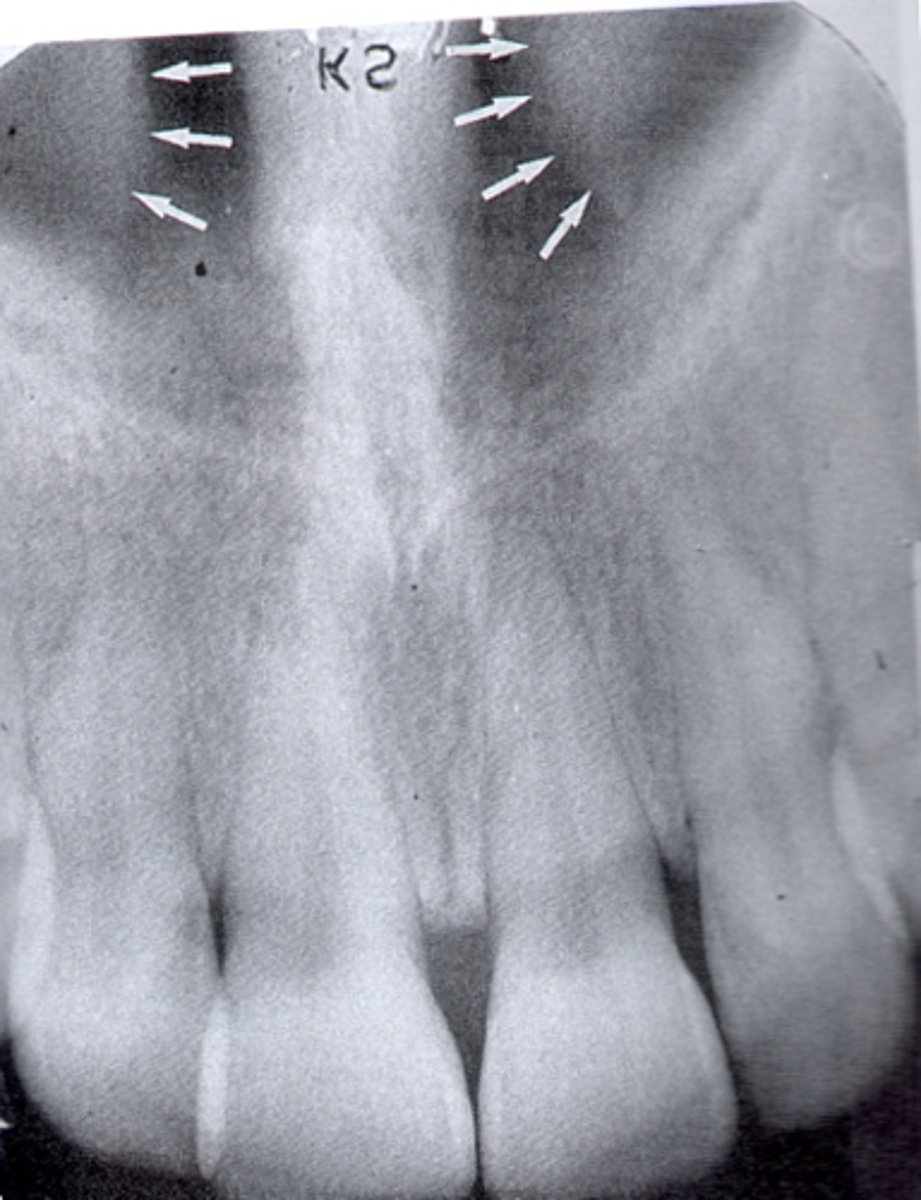

where can you see the nasal sinus in a radiograph

apices of 11/21

where can you see the nasal septum in a radiograph

where can you see the median palatine suture in a radiograph

line running the length of a palate

does the nasal sinus appear radiolucent or radiopaque in a radiograph

radiolucent

does the nasal septum appear radiolucent or radiopaque in a radiograph

radiopaque

does the median palatal suture appear radiolucent or radiopaque in a radiograph